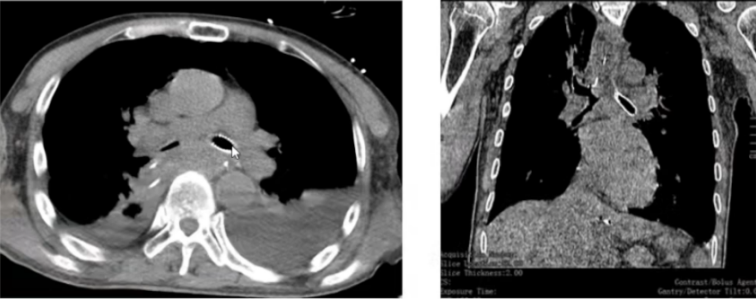

术后影像学: 左肺复张, 通气恢复(图3, 图4)

4  支架置入术后患者影像学(2021-04-29)